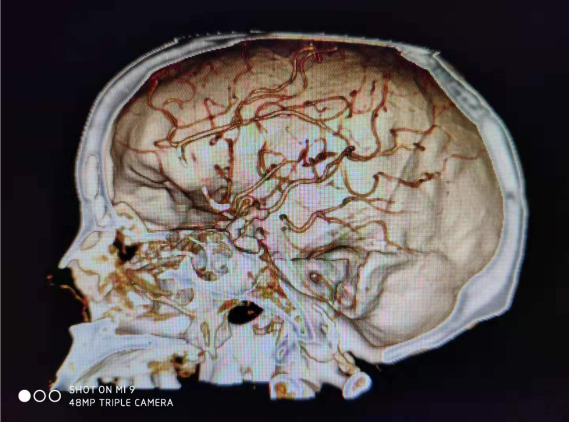

动脉瘤虽然也叫“瘤”,但它与肿瘤有本质的区别。前者只是动脉的局限性扩张,后者则有细胞增生的特征。男同视频 神经外科近期成功开展颅内动脉瘤夹闭术及动脉瘤栓塞术,填补了男同视频 在此领域的空白,为神经外科开展动脉瘤手术提供专业技术保障,为今后科室的发展迈向一个新的台阶。

病例一:患者女性,49岁,因突发意识不清2小时,伴喷射性呕吐,大汗、四肢抽搐,就诊于本院神经外科接受治疗。积极完善相关检查,患者处浅昏迷,格拉斯评分7分,CT示:左侧额颞叶脑出血,量约33ml,并急诊行CTA(血管造影)示:左侧大脑中动脉M2段动脉瘤。急诊行“颅内血肿清除术+颅内动脉瘤夹闭+去骨瓣减压”,手术顺利,目前患者治愈出院。

病例二:患者老年女性,以突发头痛收入我科,头颅CT提示:蛛网膜下腔出血,头颅CTA提示:颅内动脉瘤。急诊行脑血管造影及动脉瘤栓塞,术后患者恢复理想,已治愈出院。

动脉瘤并非绝症,治疗方式依据病人情况有保守治疗、介入和手术夹闭三种方式。总体上来讲,治愈率较高,治疗成功后也不会留下后遗症。动脉瘤介入手术在神经外科开展介入手术中具有里程碑意义,也说明了男同视频 神经外科已完全掌握了脑动脉瘤介入技术。市第一医院神经外科在崔健和王刚主任、叶妮护士长的带领下正以饱满的热情向前发展,我们始终铭记救死扶伤,有爱就有一切,为男同视频 神经外科的发展奠定坚实的基础。